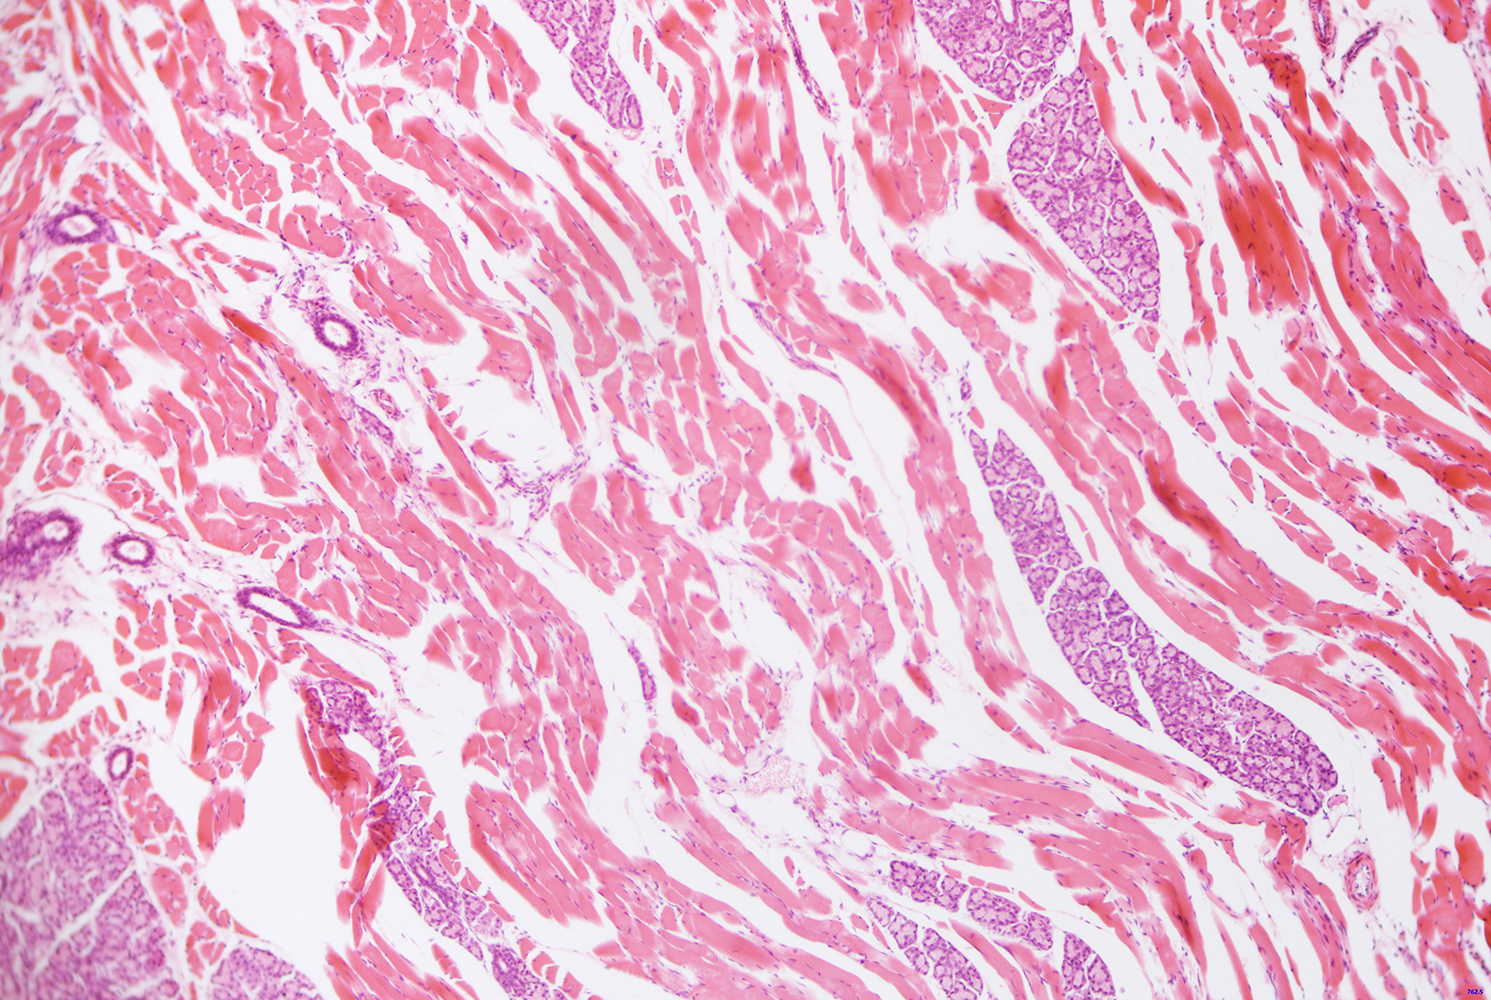

活体细胞成像,细胞或组织病理学检测,细胞学;